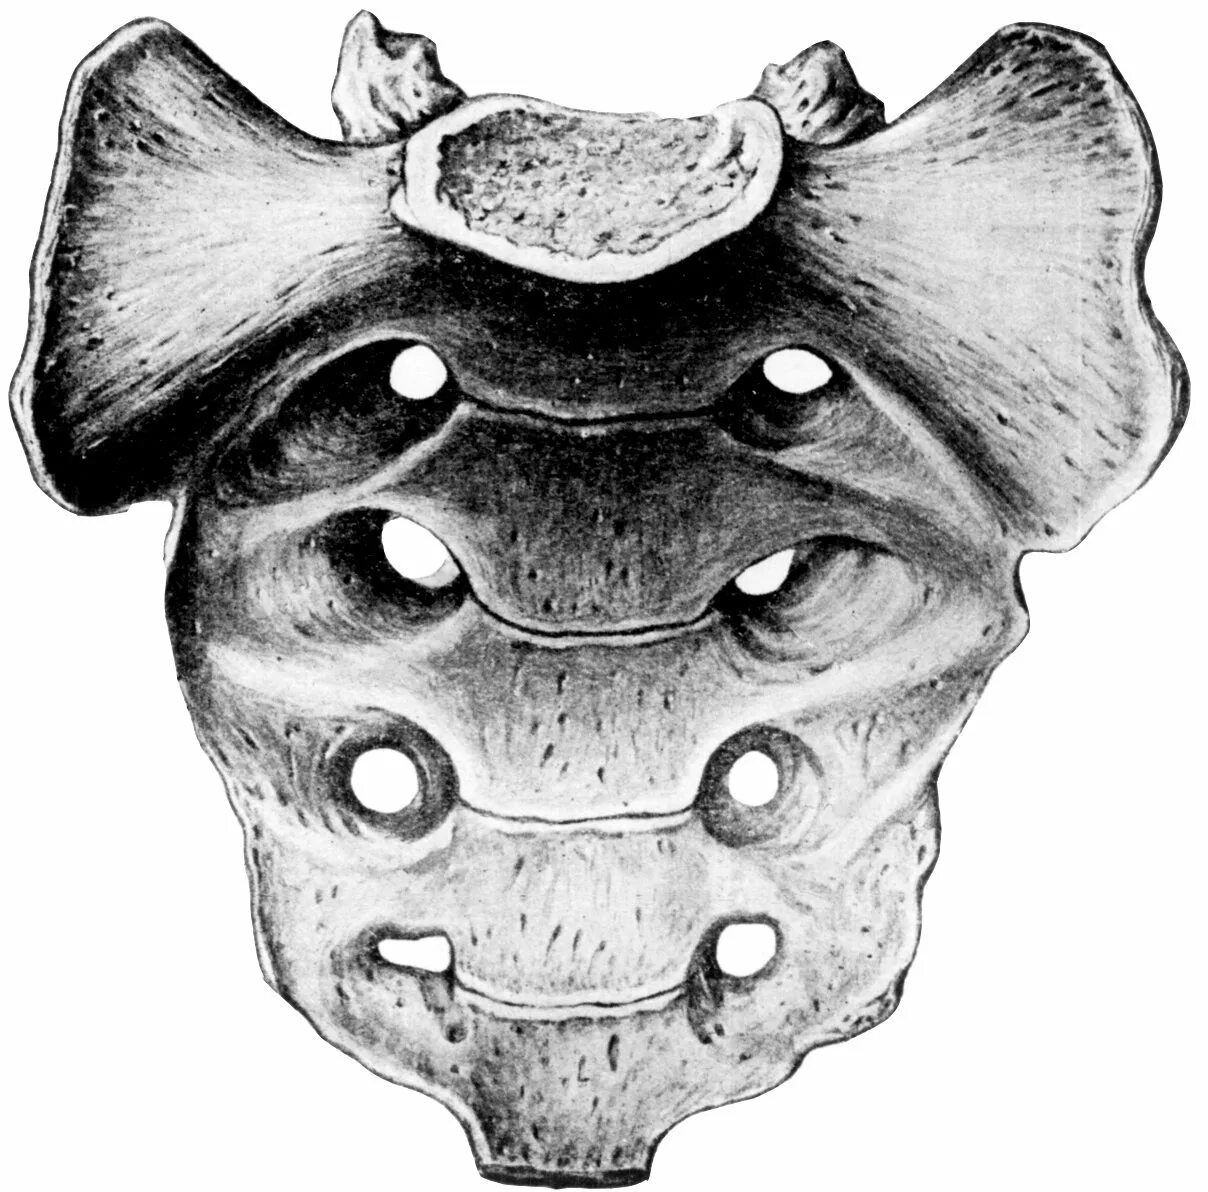

Копчик вверх